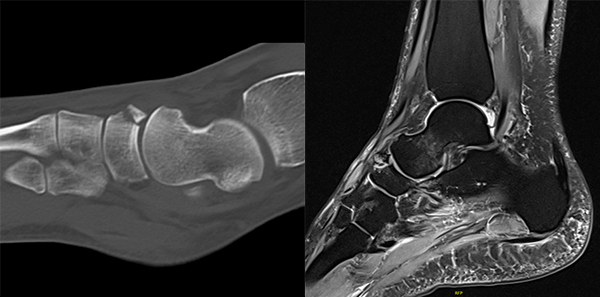

Begleitverletzungen

Häufig kommt es im Rahmen von PAC Frakturen zu knöchernen und/oder ligamentären Begleitverletzungen 20227. Eine aktuelle MRT-Studie wies in mehr als 2/3 der untersuchten Fälle Begleitverletzungen innerhalb des TN-Gelenks und in allen Fällen Verletzungen innerhalb des CC-Gelenks nach (z. B. talo-naviculare Avulsionen, Frakturen des Os cuboideum/Os naviculare, Rupturen/Avulsionsfrakturen des Lig. bifurkatum/Lig. calcaneo-cuboideum dorsale) 207. In Abbildung 1 und 2 sind häufig beobachtete Begleitverletzungen exemplarisch dargestellt.

Zum Lesen der Bildbeschreibung und zur Vollansicht bitte die Bilder anklicken. Bilder: M. Walther